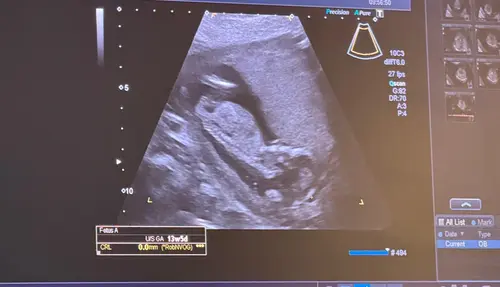

Hoi Dames,

Ik ben ook al een tijdje aan het kijken naar de Nub Theorie methode en o m g … ik kom er gewoon niet uit 🫣 hier zijn jullie een echo foto van mijn tweelingen 🤭 enig idee wat jullie met Nub kunnen zien? Ben benieuwd 🤗 veel succes voor alle aanstaande moeders/ouders 🤍💛